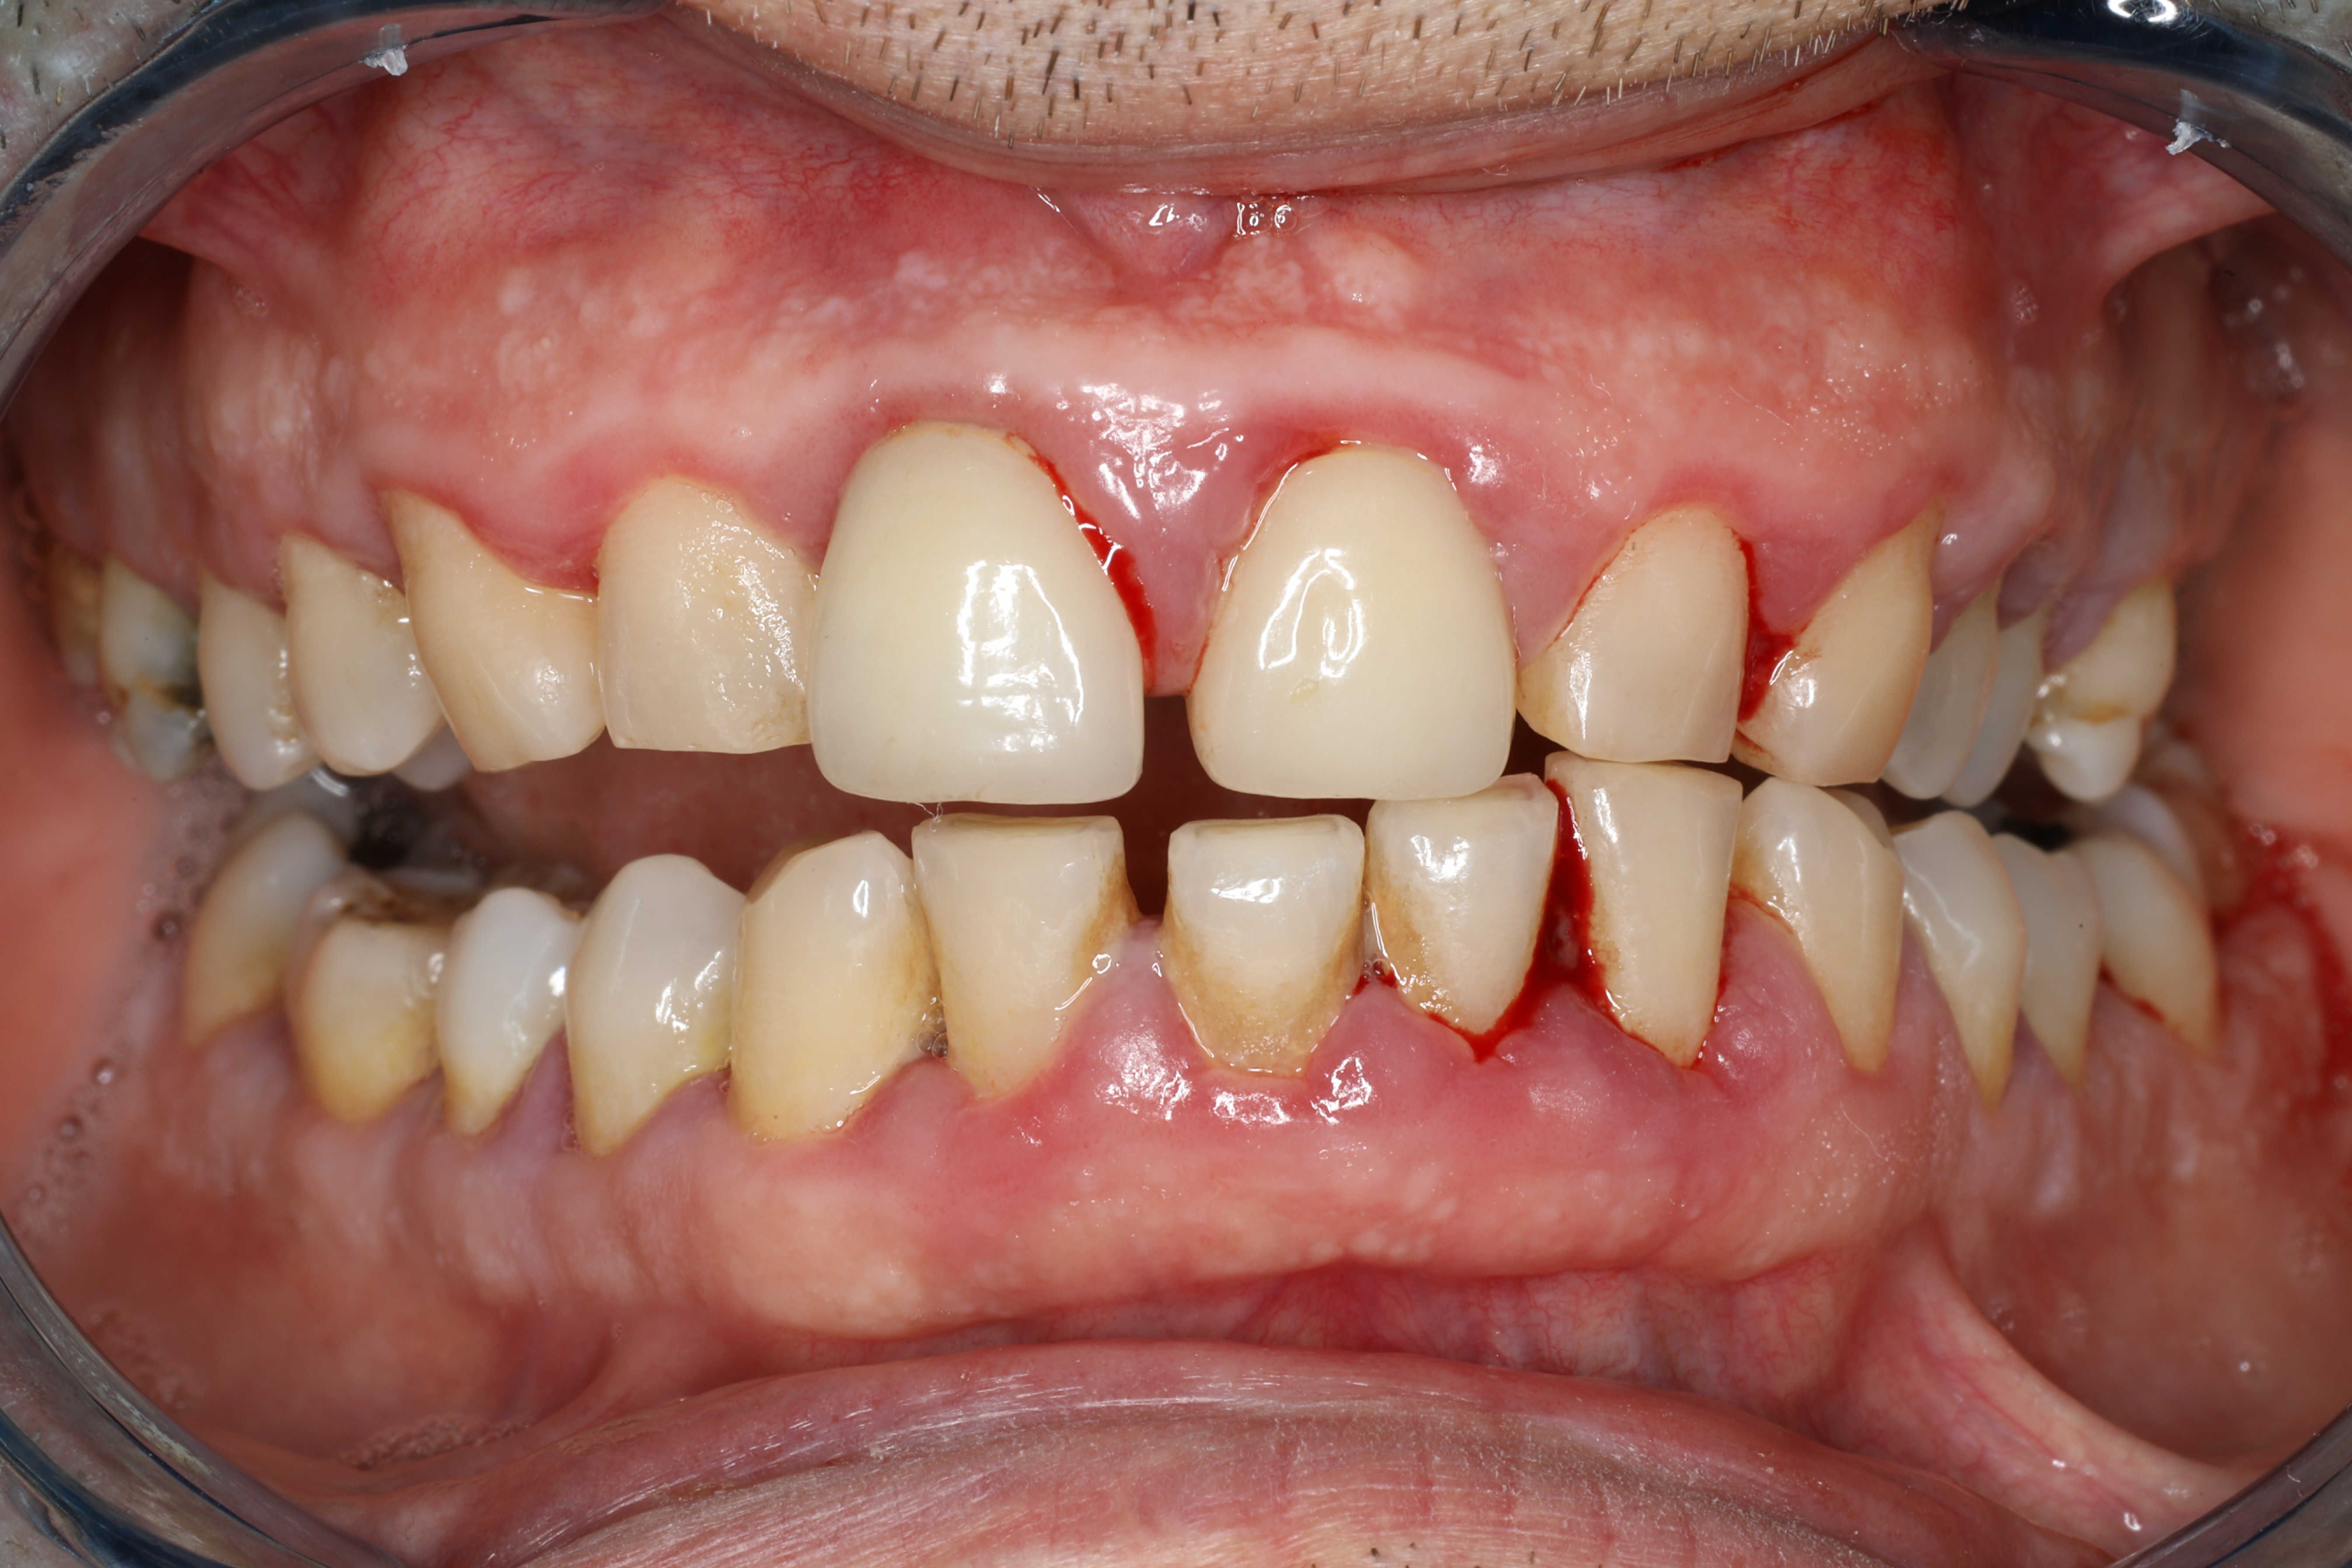

Myth 2: Bleeding Gums Are Normal

Many people believe that bleeding gums during brushing or flossing is normal. However, it's often a sign of gingivitis, the early stage of gum disease. Addressing this symptom early can prevent progression to more severe forms.